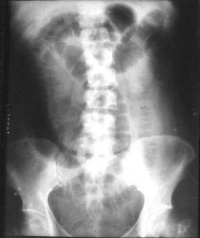

麻痹性肠梗阻

X线平片:见小肠、结肠均胀气明显。